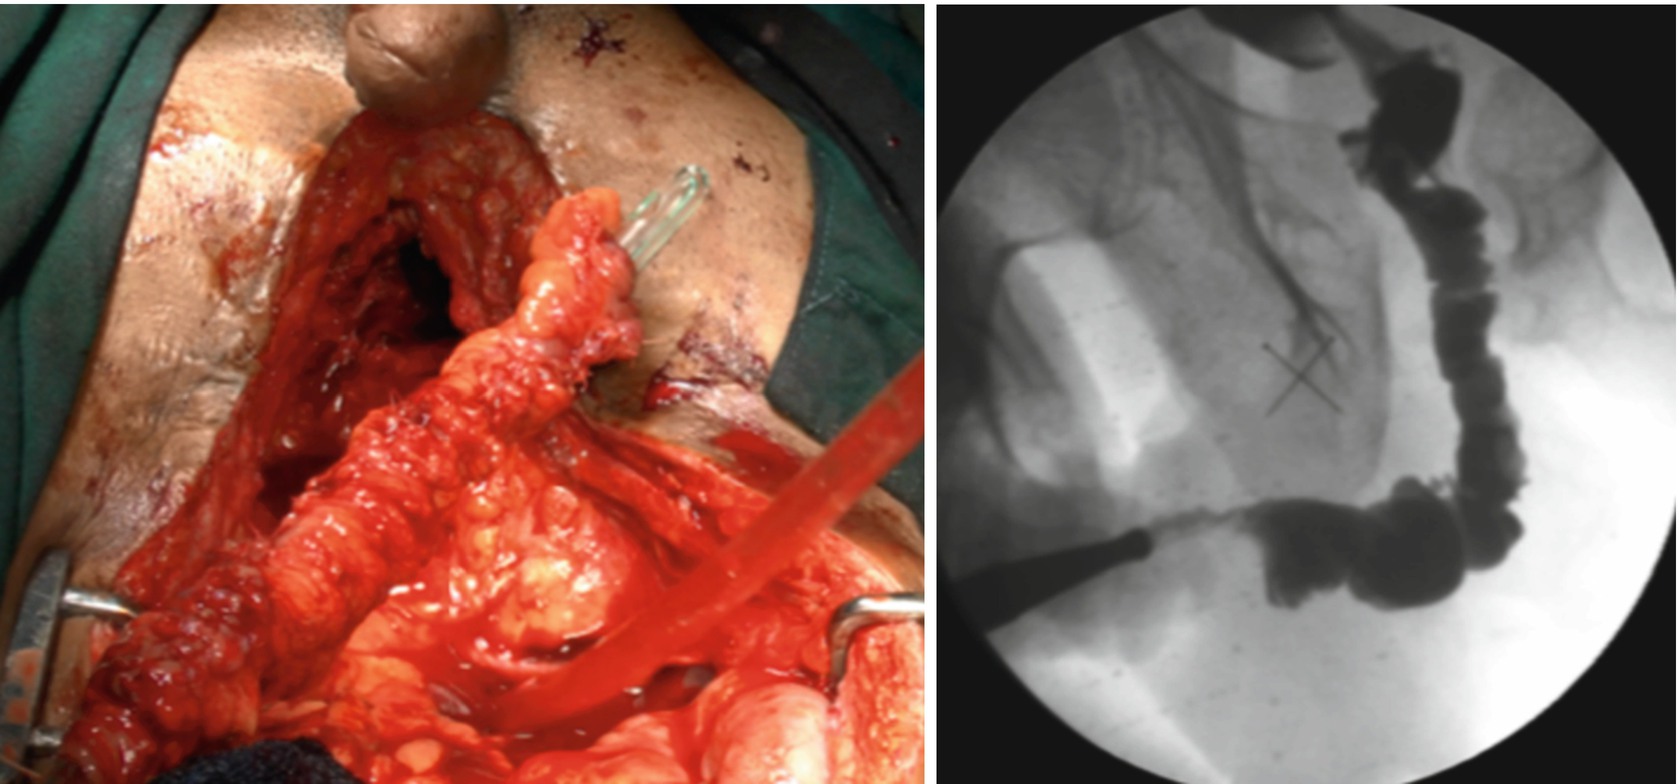

RGU and MCUG depicting bulbar urethral ischemic necrosis (BUIN)

Patient selection for these procedures is of paramount importance. The key is to evaluate which patient would benefit from urethral substitution using a bowel segment. The next challenge is to find the best suited bowel segment for the reconstruction. Usually the bowel segment with pedicle closest to the prostate is suitable. The preferred choice is the use of sigmoid colon. Patients need to admitted a day prior to urethroplasty. Bowel preparation is given and may include enema. Preoperative intravenous prophylactic antibiotics are started. Urethroplasty usually starts with a perineal incision and dissection. The healthy end of anterior urethra is identified. Crural seperation and inferior pubectomy is performed as and when necessary. In our experience, these patients often have a high bladder neck requiring a transpubic approach. This is usually performed with a infraumbilical midline incision. The initial disssection is retroperitoneal. Posterior pubectomy is performed and scar tissue excised. The posterior urethra is incised on a bougie passed from the SPC tract. This avoids opening the bladder. Once the posterior urethra is adequately freed from scar tissue, assesement of length of gap is made. The sigmoid colon is mobilised on its mesentery. The lower protion of sigmlid colon needs to be sacrificied and the upper part is swinged down on its pedicle. The sigmoid is refashioned to 26-30 Fr on a Nelatons catheter. The tailored sigmoid segment is then transposed to the perineum through abdomino perineal window. We usually keep the arch of pubic bone intact and perform inferior pubectomy (from below) and posterior pubectomy (from above). The challange is in performing the anastomosis between proximal sigmoid end and bulbo membranous junction. One trick is to keep a guide wire across the anastomosis which helps in insertion of Foleys catheter. Anastomosis is performed with 4-0 Polydiaxone suture. The distal anastomosis is done from perineum. We have additionally always mobilised omentum and wrapped around the proximal anastomosis.Clear oral fluids are started on post op day 1 as per the latest protocol. We do not keep patients fasting. Abdominal drain is kept for 5 days and once bowel movements start, drain is removed.Full oral diet is started on day 5–6. Patients are discharged on day 6–8. Catheter is removed after 6 weeks. We perform pericatheter urethrogram before removal of catheter.

We have performed urethroplasty in 115 patients of bulbar urethral necrosis. Amongst these, we performed enetrourethroplasty using sigmoid colon in 3 patients with 100% success [7].